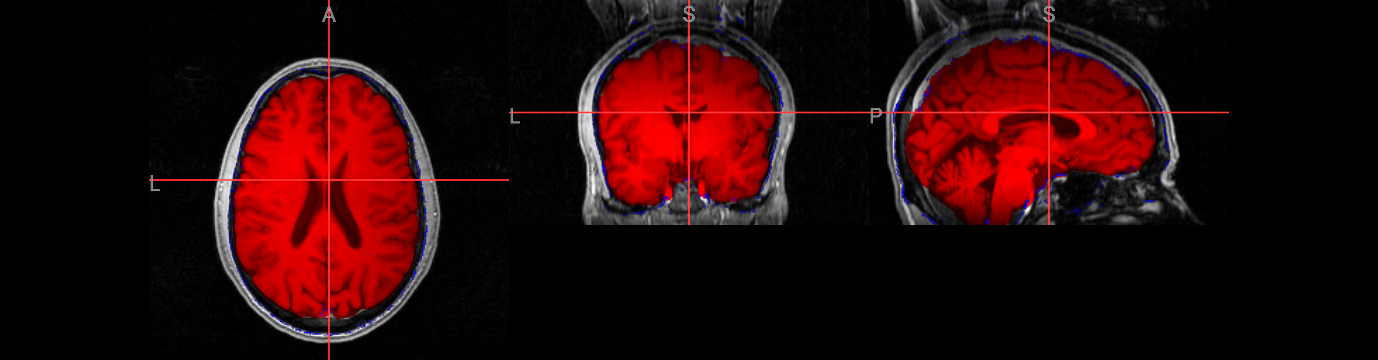

Visualization with ipyniivue#

from ipyniivue import NiiVue

nv = NiiVue()

nv.load_volumes( [{"path": "./fsl_course_data/intro/structural.nii.gz", "colormap": "gray"},

{"path": "./output/structural_brain.nii.gz", "colormap": "red" },

{"path": "./output/structural_brain_skull.nii.gz", "colormap": "blue" }])

nv

from IPython.display import Image

Image(url='https://raw.githubusercontent.com/NeuroDesk/example-notebooks/refs/heads/main/books/images/fsl_course_bet05.png')